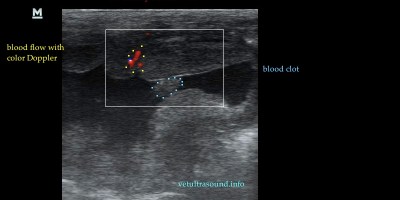

Κατηγορία: Abdominal Ultrasound